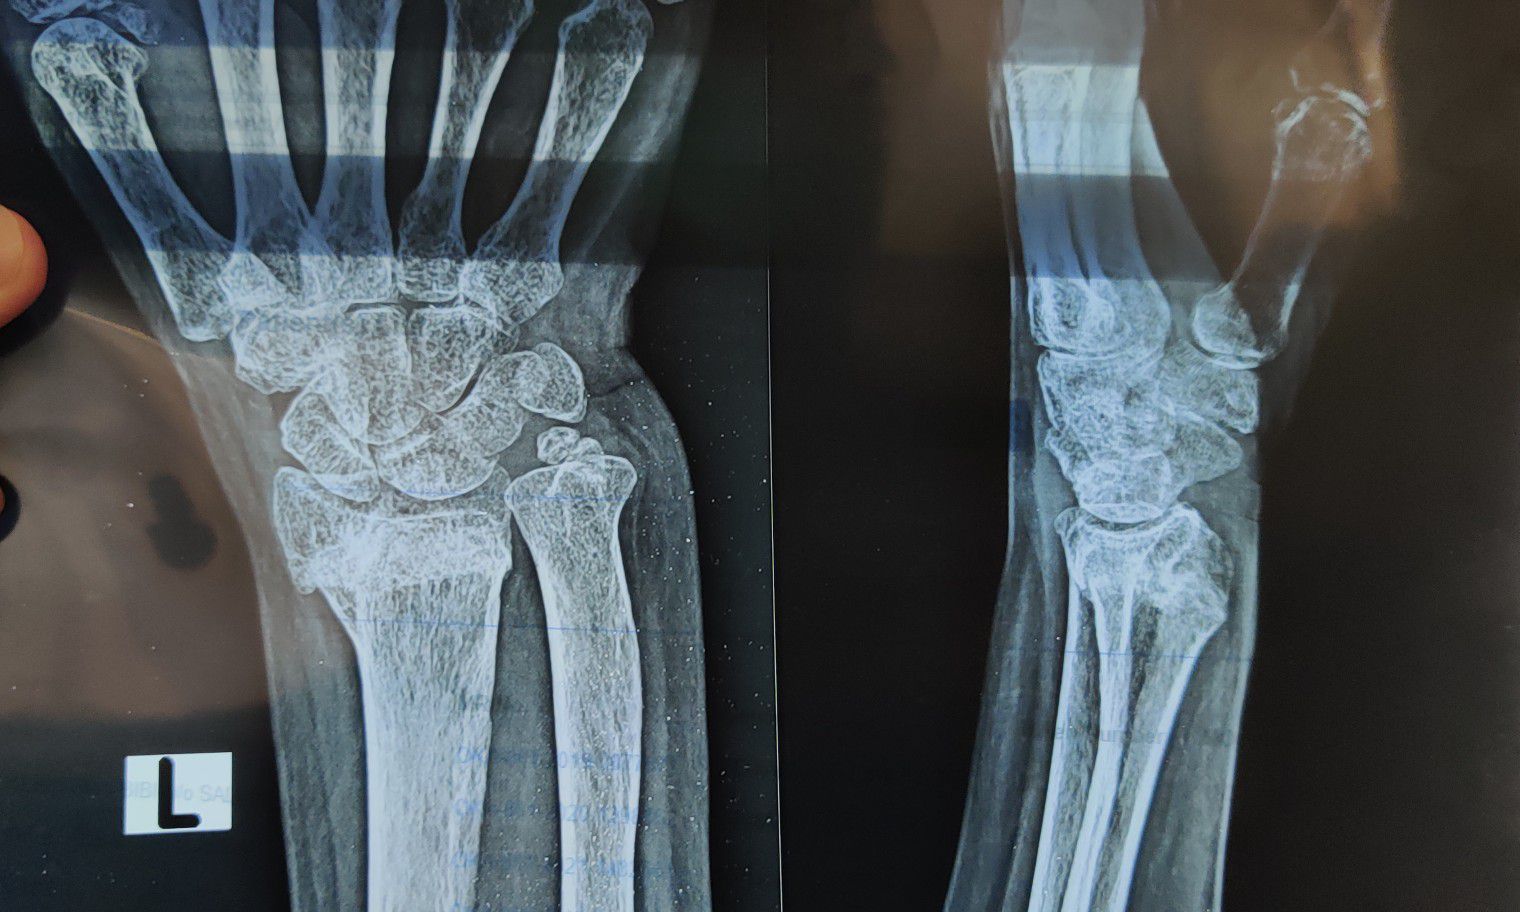

Fracture of Radius

Xray

Orthopaedics

Radius